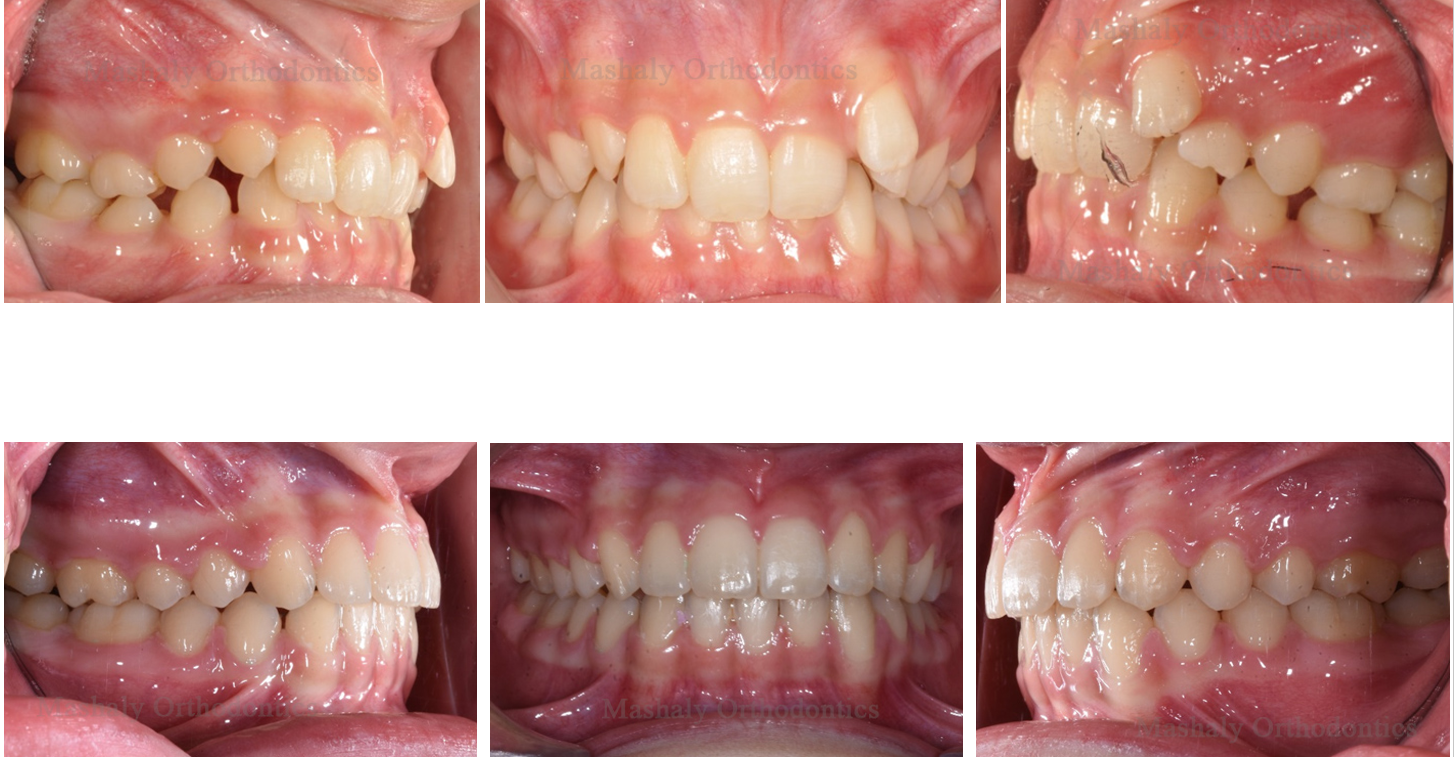

Orthodontics is a dental specialty that helps treat misalignment of teeth, malocclusion

(improper bite), and other related issues. Orthodontic treatment goes beyond addressing cosmetic concerns and is also used to treat various medical conditions such as impacted teeth and other dental problems.